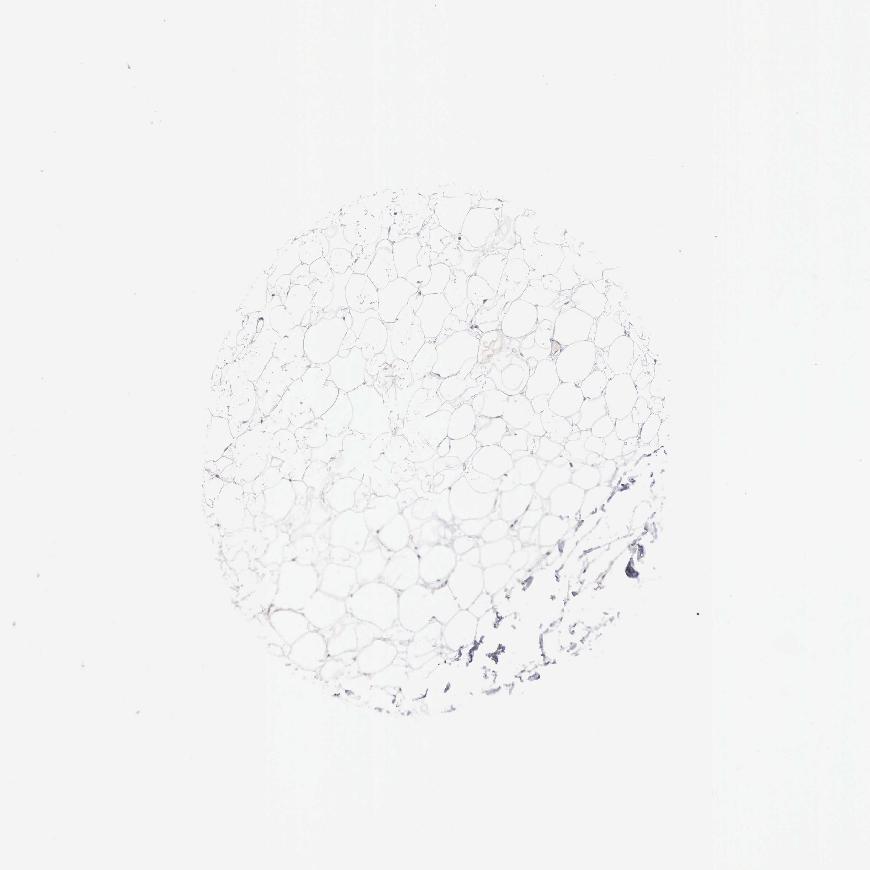

SOFT TISSUE 2 - Antibody stainingi

Antibody staining in the annotated cell types in the current human tissue is reported as not detected, low, medium, or high, based on conventional immunohistochemistry profiling in selected tissues. This score is based on the combination of the staining intensity and fraction of stained cells.

Each image is clickable and will lead to virtual microscopy that enables deeper exploration of all samples and also displays staining intensity scores, fraction scores and subcellular localization as well as patient and tissue information for each sample.

Antibody HPA000431

Fibroblasts Not detected